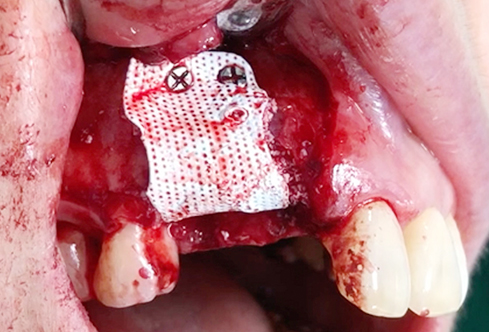

A surgical procedure using non resorbable membrane

• A surgical procedure using non resorbable membrane 1